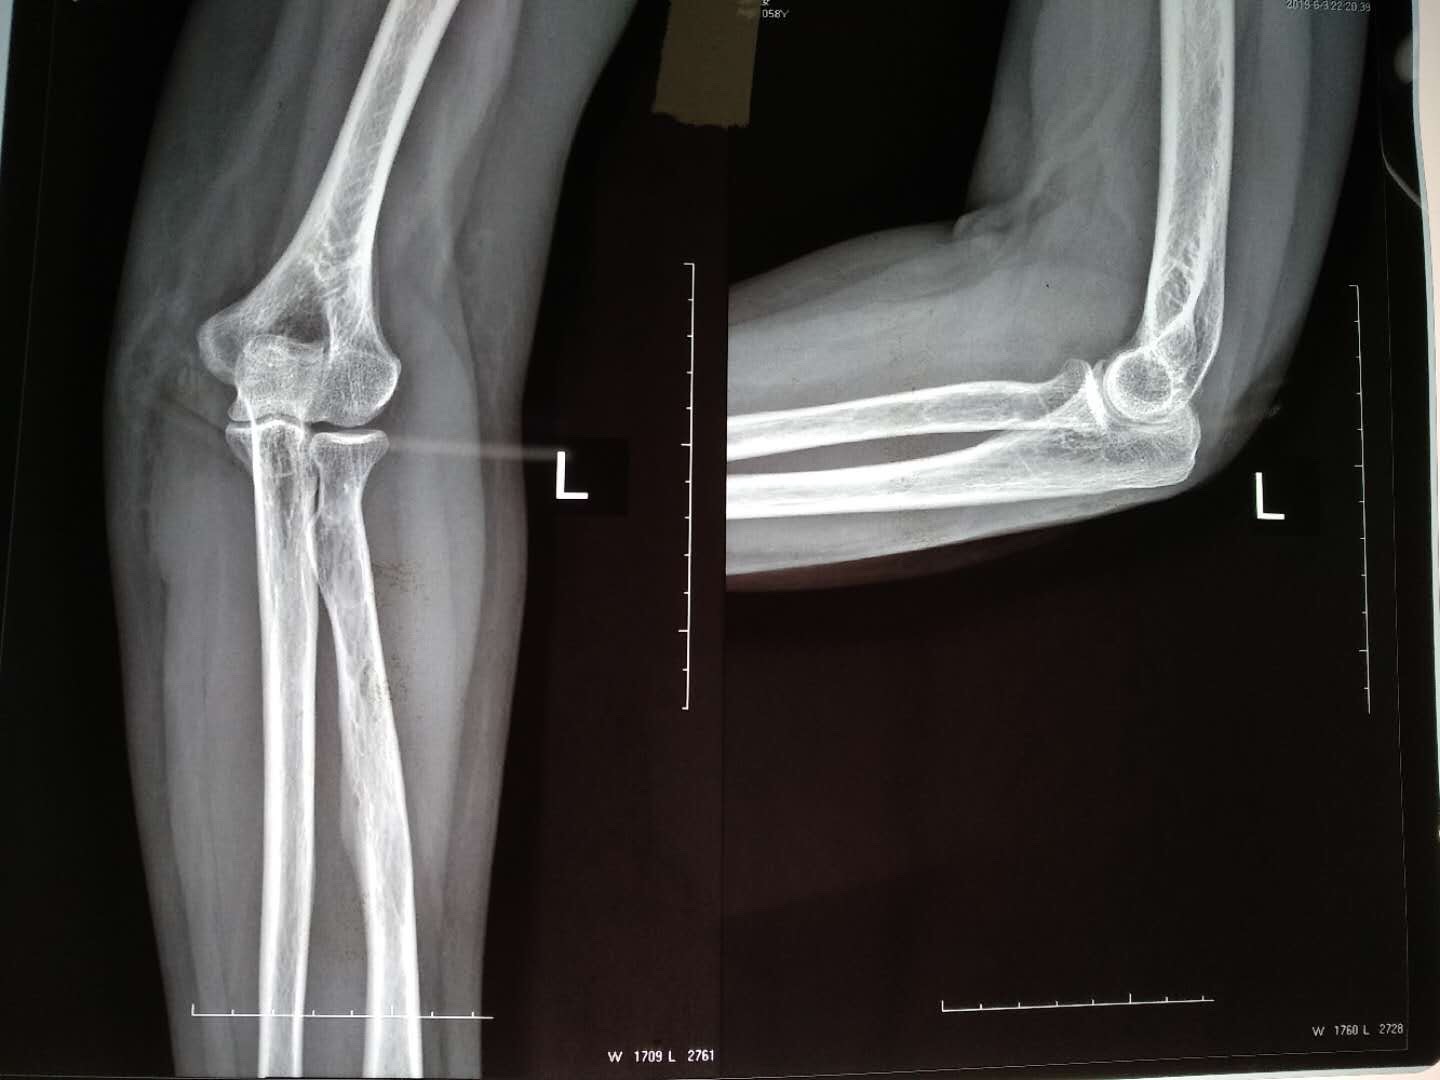

肱骨内髁屈肌腱总止点撕脱性骨折(止点重建,尺神经松解

摔伤后左肘部肿痛,活动受限1小时入院。既往身体健康,无特殊不良嗜好。

生命体征平稳,心肺复未见异常。左肘部肿胀明显,局部皮色发红,皮温高,压痛明显,肘关节侧搬试验内侧阳性,末梢血运正常,尺神经只配区稍感麻木。

诊断        左肱骨内髁屈肌腱总止点撕脱性骨折,   尺神经损伤在臂丛麻醉下行切复内固定,止点重建,尺神经松解术,术后石膏托固定,抗炎,消肿等处理。